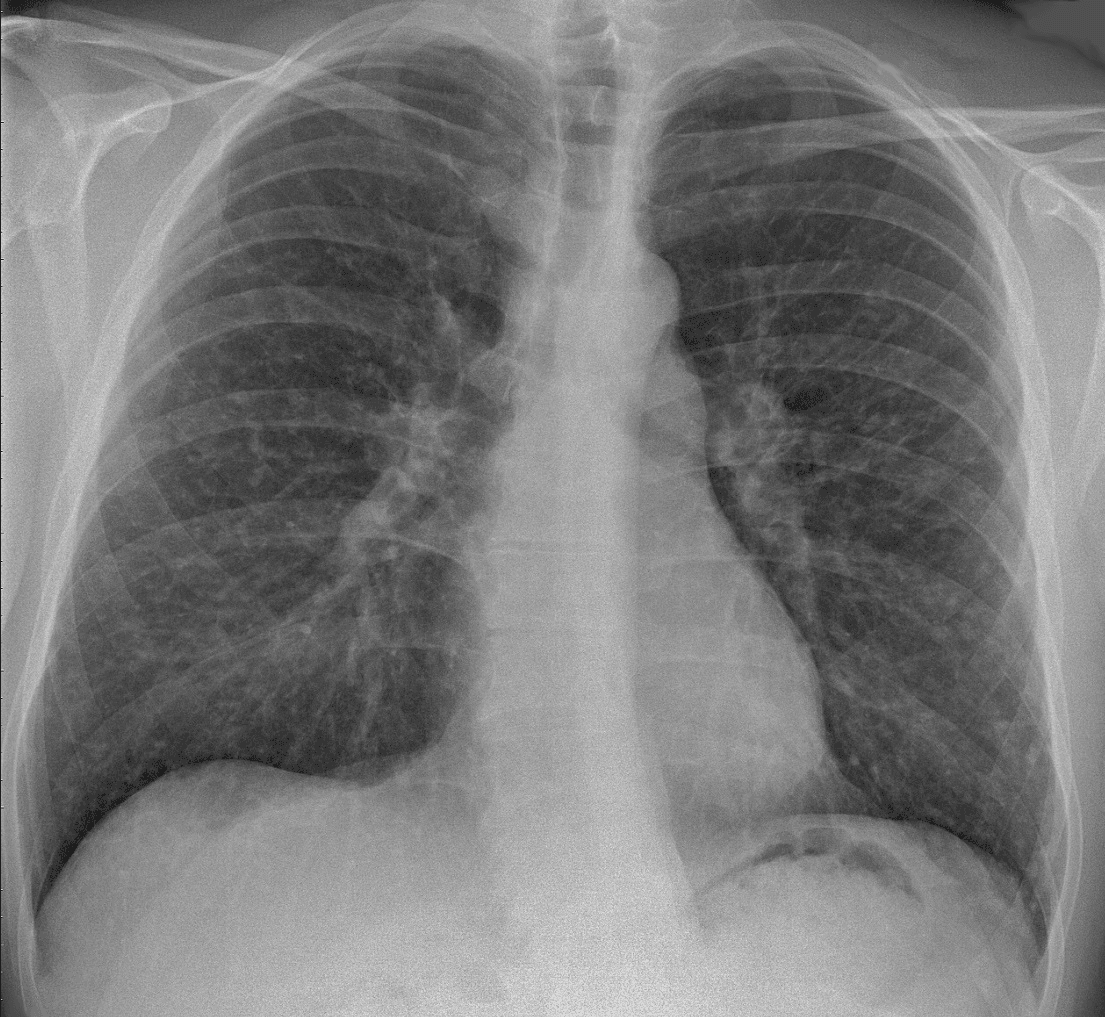

Sarcoidosis (also known as Besnier–Boeck–Schaumann disease) is a disease involving abnormal collections of inflammatory cells that form lumps known as granulomata. The disease usually begins in the lungs, skin, or lymph nodes. Less commonly affected are the eyes, liver, heart, and brain, though any organ can be affected. The signs and symptoms depend on the organ involved. Often, no, or only mild, symptoms are seen. When it affects the lungs, wheezing, coughing, shortness of breath, or chest pain may occur. Some may have Löfgren syndrome with fever, large lymph nodes, arthritis, and a rash known as erythema nodosum. The cause of sarcoidosis is unknown. Some believe it may be due to an immune reaction to a trigger such as an infection or chemicals in those who are genetically predisposed. Those with affected family members are at greater risk. Diagnosis is partly based on signs and symptoms, which may be supported by biopsy. Findings that make it likely include large lymph nodes at the root of the lung on both sides, high blood calcium with a normal parathyroid hormone level, or elevated levels of angiotensin-converting enzyme in the blood. The diagnosis should only be made after excluding other possible causes of similar symptoms such as tuberculosis. Sarcoidosis may resolve without any treatment within a few years. However, some people may have long-term or severe disease. Some symptoms may be improved with the use of anti-inflammatory drugs such as ibuprofen. In cases where the condition causes significant health problems, steroids such as prednisone are indicated. Medications such as methotrexate, chloroquine, or azathioprine may occasionally be used in an effort to decrease the side effects of steroids. The risk of death is 1–7%. The chance of the disease returning in someone who has had it previously is less than 5%. In 2015, pulmonary sarcoidosis and interstitial lung disease affected 1.9 million people globally and they resulted in 122,000 deaths. It is most common in Scandinavians, but occurs in all parts of the world.